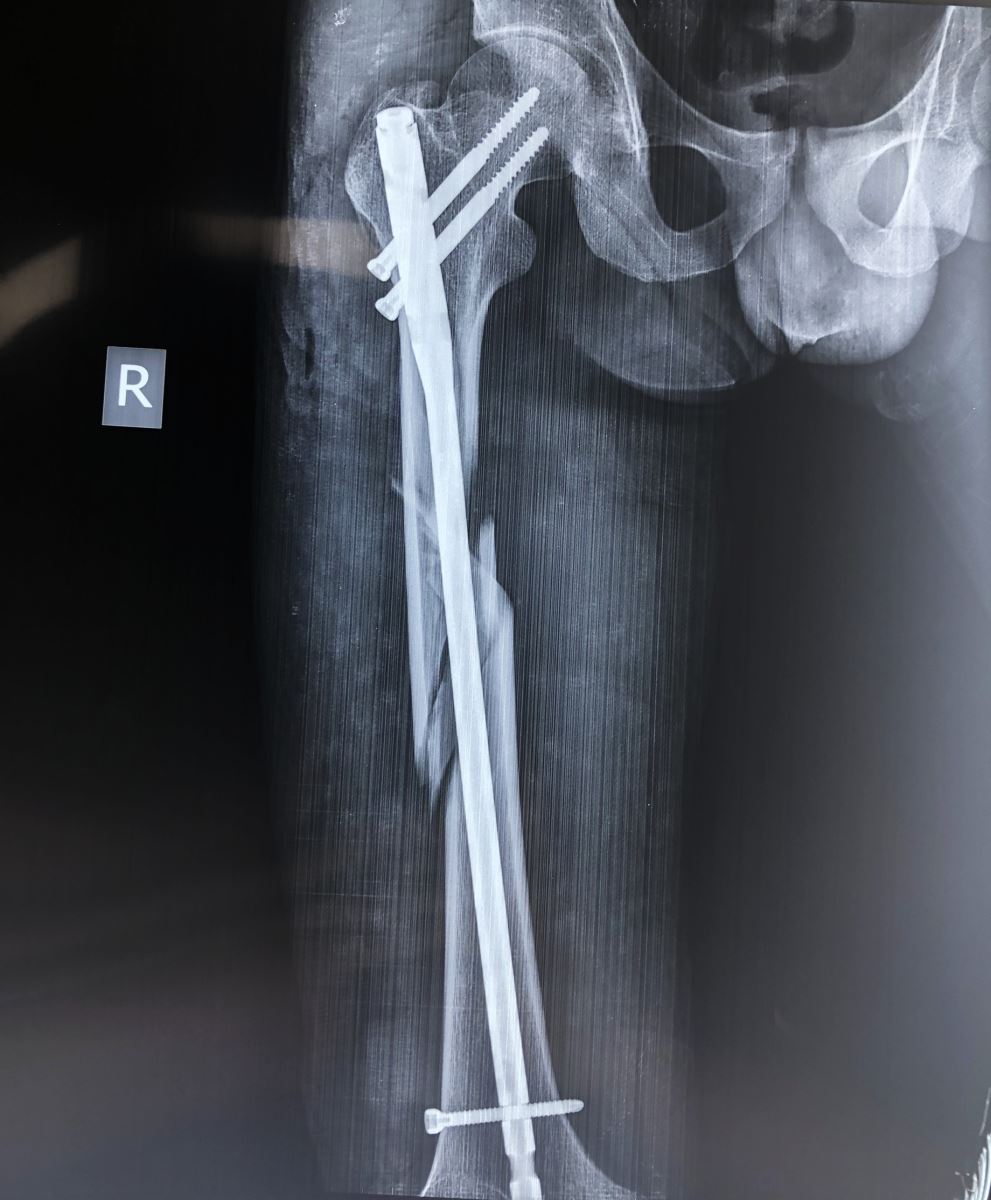

Đóng đinh nội tủy:

Áp dụng cho các trường hợp gãy thân xương đùi, tốt nhất đoạn 2/4 giữa, áp dụng trong tất cả các trường hợp gãy ngang, chéo, nhiều mảnh, gãy 2 ổ. Đóng đinh nội tủy được xem là phương pháp tốt nhất hiện nay. Nhờ màn tăng sáng, người ta đóng đinh không mở ổ gãy và có khoan rộng ống tủy. Để chống xoay của đoạn gãy xa người ta tăng cường chốt ngang qua xương. Trong trường hợp đường gãy thấp ở đoạn 1/3 giữa và dưới, có thể tiến hành đóng đinh nội tủy có chốt ngang ngược dòng từ đầu dưới xương đùi.